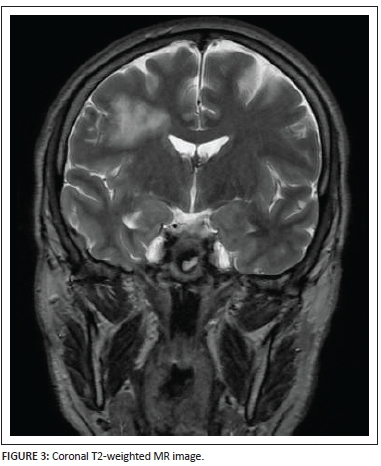

The location of the lesion is well shown on the coronal T2-weighted image (Figure 3) as well as the extent of the lesion from the juxta-ventricular margin up to the subcortical white matter.